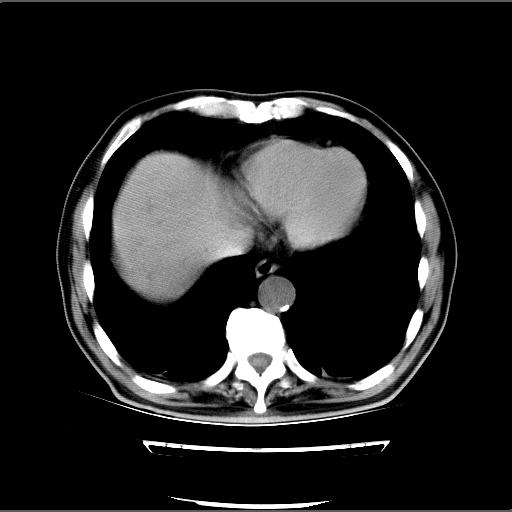

患者男82岁,黄染,发热10天,无腹痛。

1胆总管下端结石伴肝内外胆管扩张;2胆囊颈部结石伴胆囊积液

胆囊多发结石,胆囊积液;胆总管中下段结石,中上段扩张。

胆总管下段结石伴胆道系统扩张;胆囊炎伴胆囊结石.

此病例有结果了:患者术后为:胆总管下段结石伴胆道系统扩张;胆囊炎伴胆囊结石。

各位战友分析的都很正确,是一个典型的病例。